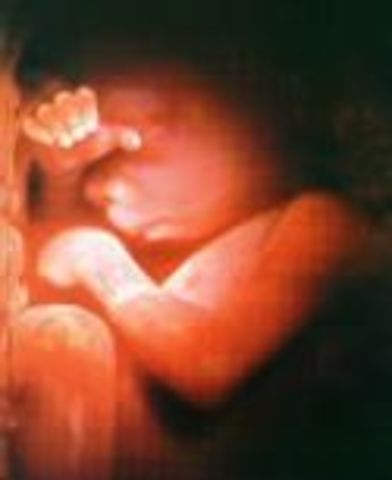

• week 27

week 27

Looks are almost fully developed. Retina at the back of baby's eyes are starting to develop.

• week 28

week 28

Eyes are starting to move in their sockets. Can recognize your voice.